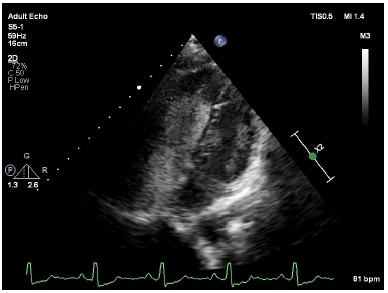

Transthoracic echocardiography showed dilated right atrium, right ventricle with a large atrial septal defect (ASD) with bi-directional shunt and severe pulmonary valve stenosis (Figures 2–4). Bubble's study confirmed the diagnosis of atrial septal defect (Figure 5) Parasternal long-axis view M-mode showed right ventricular hypertrophy of 9mm (Figure 6). Further plan for trans-esophagealechocardiography was discussed with patient but due to financial constraints as a foreigner, he decided to continue investigations in his home country. The patient was rehydrated with intravenous fluid therapy and was discharged with referral letter to home country.

Figure 5 Bubble study showing presence of bubble in left ventricle at early cardiac cycle indicating right to left shunt and flow of blood pushing bubbles at right ventricular indicating left to right shunt. (Bidirectional shunt).